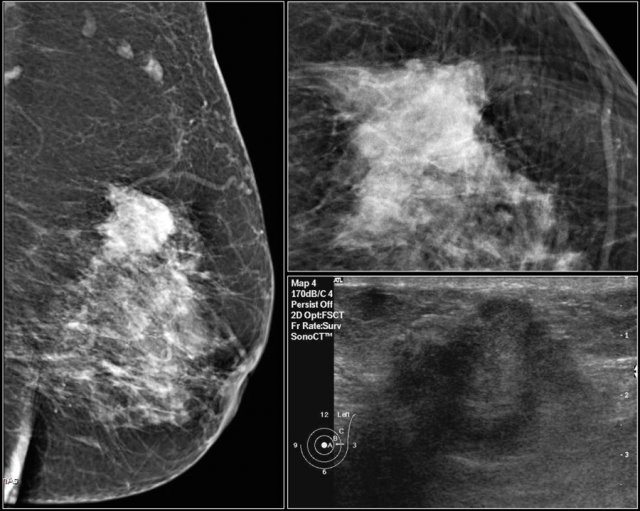

First study the images and describe the findings.

Then continue reading.

The findings are:

• Mass with irregular shape.

• Spiculated margin.

• High density.

• Ultrasound also shows irregular shape with indistinct margin.

This mass is categorized as BI-RADS 5.